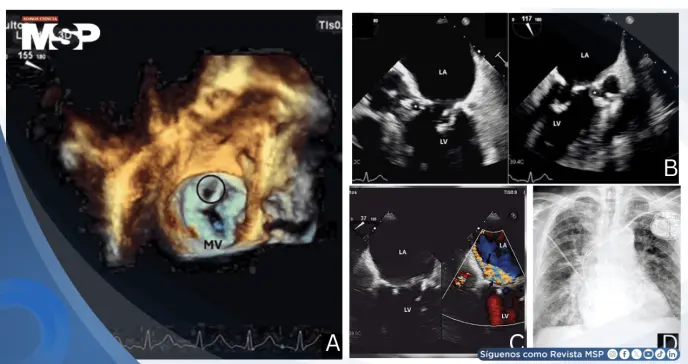

La ecocardiografía transtorácica identificó una válvula mitral fibrocalcificada con estructura móvil filiforme e insuficiencia mitral excéntrica significativa. La ecocardiografía transesofágica (ETE) reveló el hallazgo crítico: un pseudoaneurisma subvalvular aórtico originado en la fibrosa del intervalo mitral-aórtico (MAIVF).

La ETE tridimensional demostró además una amplia perforación del velo mitral posterior (segmento P2) con segmento en flagelo, causando regurgitación mitral grave con efecto Coanda dirigido hacia el tabique interauricular.

Este caso resalta el valor diagnóstico de la ecocardiografía transesofágica tridimensional para identificar complicaciones estructurales complejas de la endocarditis infecciosa.